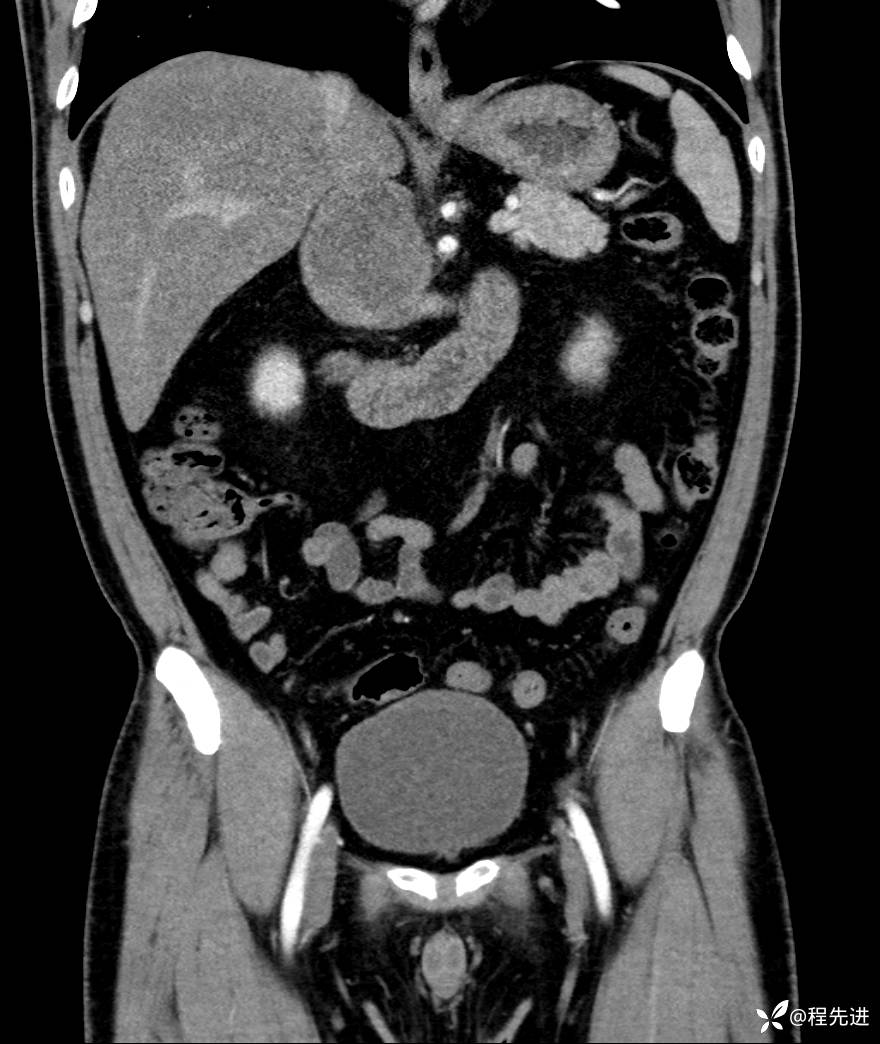

【腹盆】特别精彩病例|发现腹膜后肿物1月余

主诉:发现腹膜后肿物1月余

现病史:患者1月余前查体,行超声检查提示:后腹膜囊实性肿块;慢性胆囊炎伴胆囊内结石;无腹痛腹胀,不伴腹泻发热等;偶感腰背部酸痛。

CT平扫+增强: